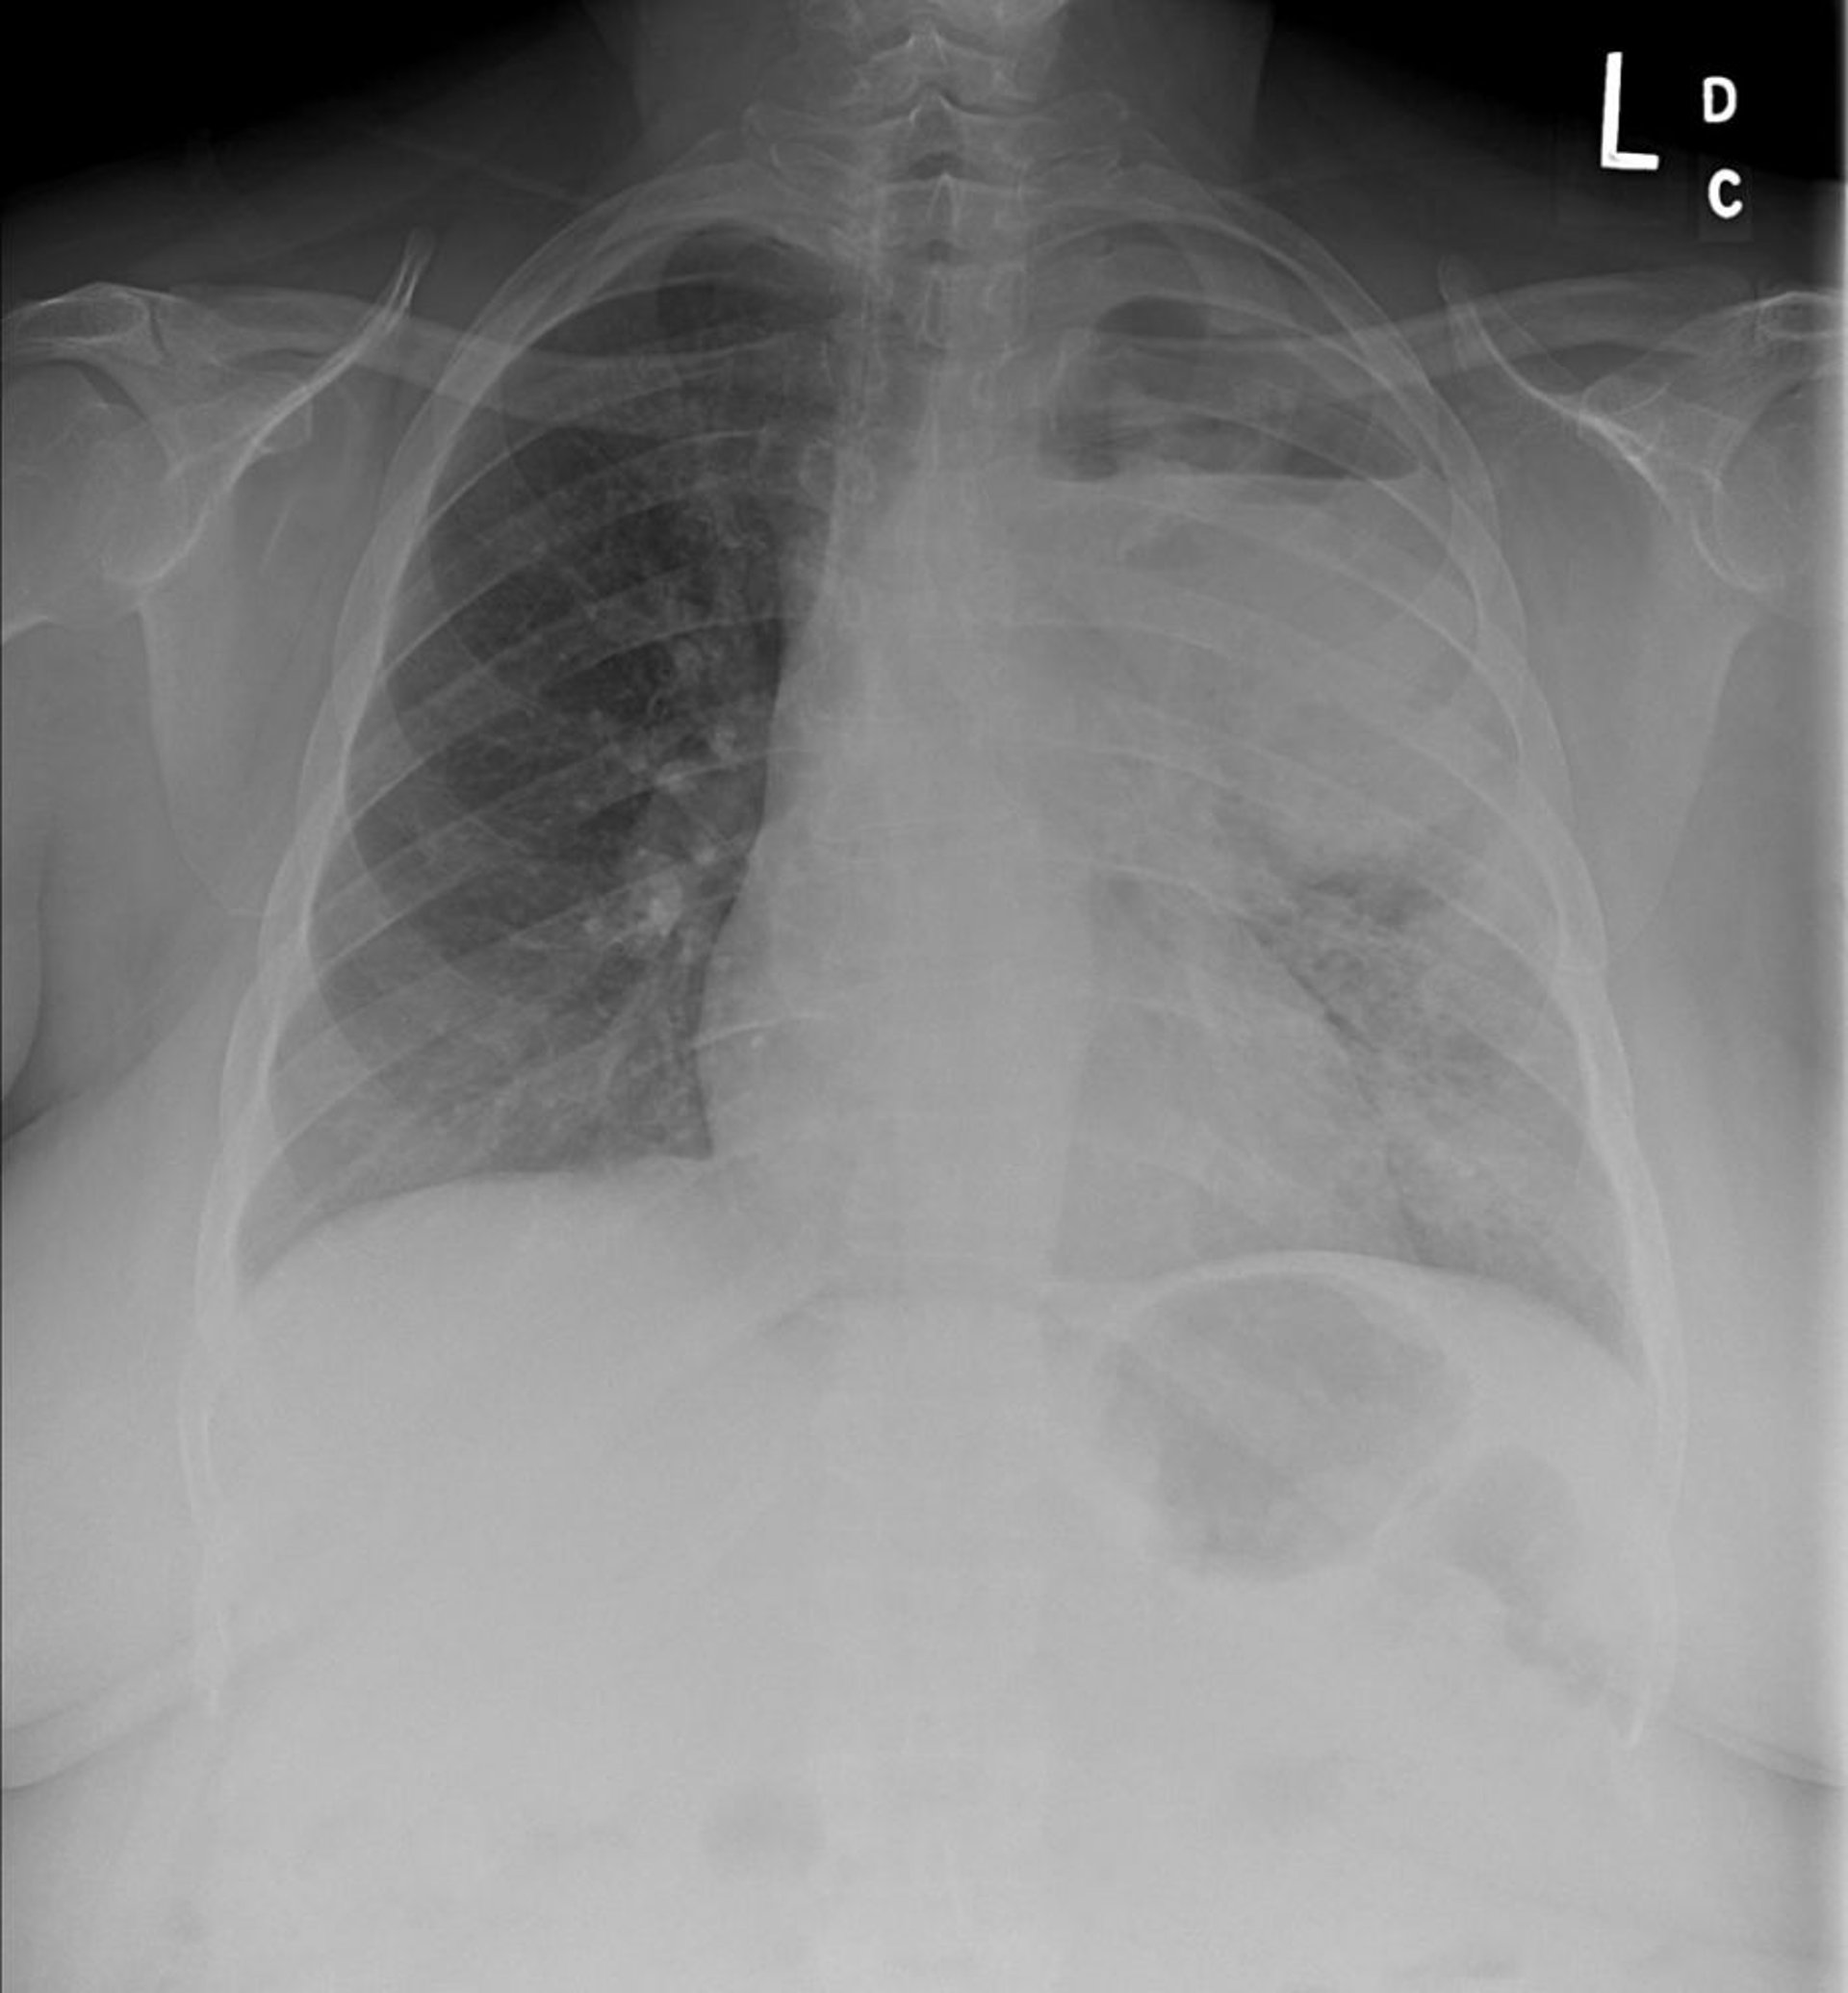

• Röntgenthorax

Das erste bildgebende Verfahren ist oft eine Röntgenthoraxaufnahme. Es können sich klar definierte pathologische Befunde zeigen: z. B. solitäre, multifokale Tumoren, ein solitärer pulmonaler Rundherd, ein vergrößerter Hilus, ein verbreitertes Mediastinum, tracheobronchiale Verengungen, Atelektasen, persistierende parenchymale Infiltrate, Kavernen oder unerklärliche Pleuraverdickungen oder -ergüsse. Diese Befunde sind suggestiv, jedoch nicht diagnostisch für einen Lungenkrebs und erfordern weiterführende CT-Scans oder kombinierte PET-CT und eine zytopathologische Diagnosesicherung.